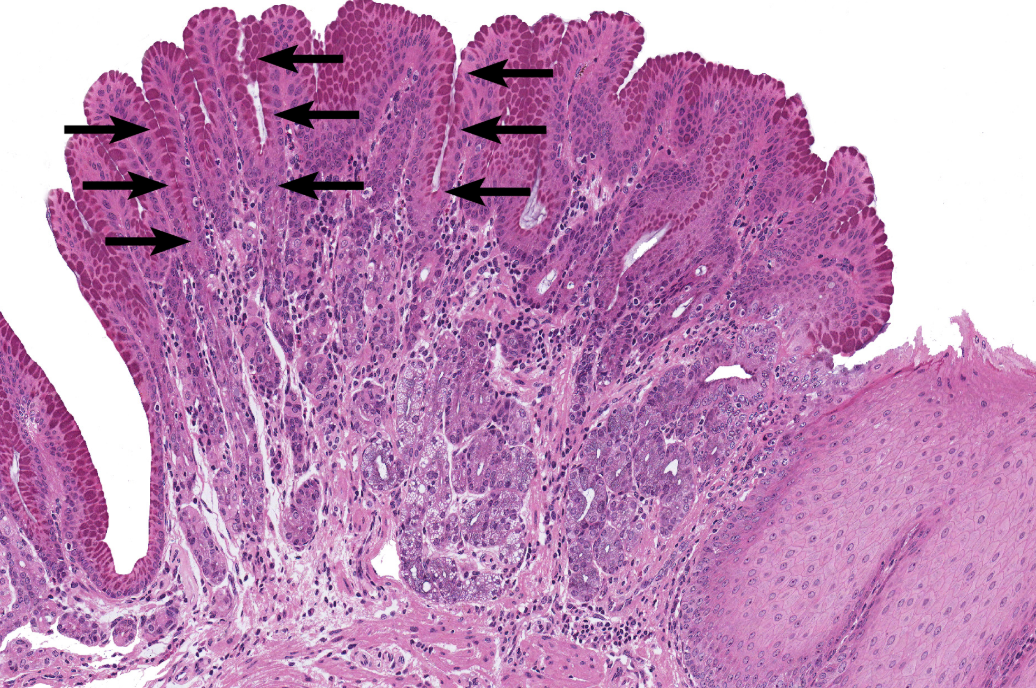

Stomach

NOTICE: THE DEEP GASTRIC PITS WITH DARK STAINED GASTRIC GLANDS AROUND THEM AND NOT MANY GOBLET CELLS